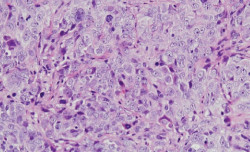

Investigadores del CSIC identifican una proteína implicada en la supervivencia de las pacientes con cáncer de ovario

Una investigación, liderada por la investigadora del Centro de Investigación del Cáncer (Universidad de Salamanca-CSIC), del Instituto de Investigación Biomédica de Salamanca (IBSAL), y del CIBER de Cáncer, Azucena Esparís-Ogando, ha identificado que la activación anormal de la proteína WNK1 afecta drásticamente a la supervivencia de las pacientes con cáncer de ovario y permite evaluar la eficacia preclínica de nuevas terapias para tratar esta enfermedad.